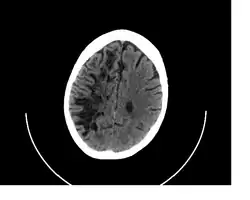

CT image showing extensive low attenuation in the right hemispheric white matter due to dilated Type 2 perivascular spaces